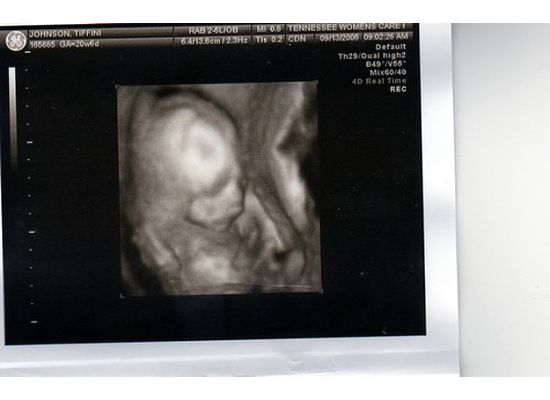

Alight Bella-Grace. January 15, 2007, 4:27pm. 1/2 ounce shy of being 8 lbs. She is spirited, she is soft spoken. She is funny. She is beautiful. She makes lists of her favorite rides at Beech Bend. She is a thrill seeker–she wants to go as fast on rides as she can. She loves her older sister. She is gifted at gymnastics and using her hands. She is a snuggle bunny. She is precious.